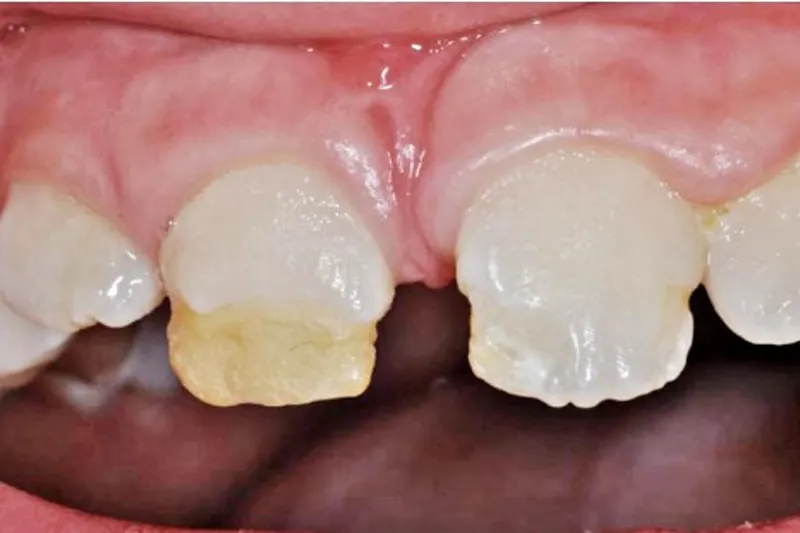

Velafgrænsede hvide eller gulbrune opaciteter i emaljen er de hyppigst forekommende defekter og ses hos ca. 20 % af alle børn, der har haft et traume i det primære tandsæt.

Traumer i det primære tandsæt forekommer hyppigt. Ca. hvert tredje barn oplever et traume i førskolealderen. Incidensen er størst i 2-3-årsalderen, hvor den permanente tandkrone endnu ikke er færdigmineraliseret. På grund af den tætte relation mellem roden på den primære tand og det permanente tandkim er der risiko for, at traumet på den primære tand påvirker udviklingen af den permanente tand. Risikoen for disse udviklingsdefekter afhænger af den permanente tands udviklingsstadie samt traumets omfang og retning. Velafgrænsede hvide eller gulbrune opaciteter er den hyppigst forekommende type af defekt og ses hos ca. 20 % af alle børn, der har haft et traume i det primære tandsæt. Alvorlige malformationer såsom kronedilaceration, afvigelser i roddannelsen og odontomdannelse er sjældne (< 6 %) og ses oftest som følge af intrusion, avulsion (eksartikulation) eller fraktur af processus alveolaris hos børn i 0-3-årsalderen. Incisiver med alvorlige malformationer har ofte behandlingskrævende eruptionsafvigelser, og da behandling af tandens krone ligeledes kan være påkrævet kort efter eruption, bør disse patienter følges nøje i forbindelse med det forventede eruptionstidspunkt. Det er vigtigt så vidt muligt at bevare malformerede tænder af hensyn til udvikling og bevarelse af processus alveolaris.